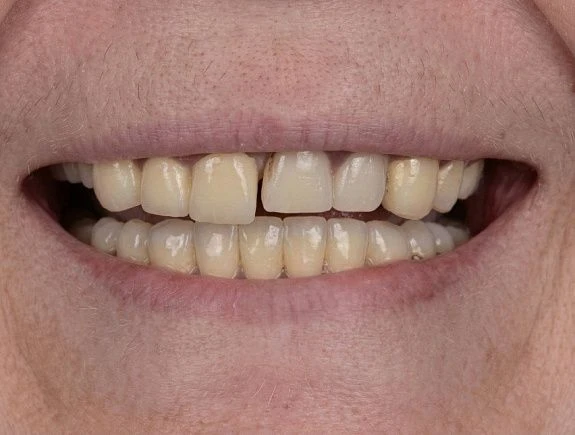

Наши работы